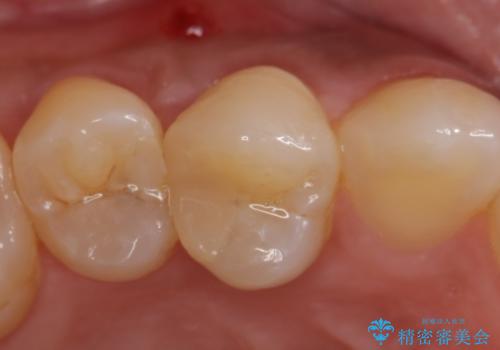

右上4は根管治療を行い、オールセラミッククラウンによる補綴を行いました。

今回用いたオールセラミッククラウンはジルコニアフレームという白い素材の上にセラミックを盛っているため、審美性が非常に高いのが特徴です。

また、ジルコニアは人工ダイヤモンドの材料にも使われているほど高い強度を持っており、そのためオールセラミッククラウンは審美性だけでなく、奥歯やブリッジの補綴も可能とするクラウンです。